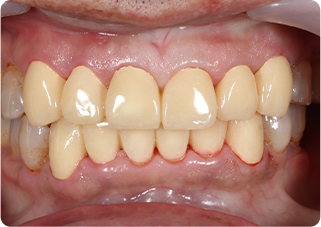

セラミッククラウン症例①

術前

仮歯

技工物

術後

| 主訴 | 見た目を綺麗にしてほしい |

|---|---|

| 治療期間/回数 | 3ヵ月、5回 |

| 価格(税込) | 363,000円(税込) |

| リスク・副作用 | セラミック破損の可能性 |

| ポイント | 自然な色、形となるようにオーダーメイドでセラミックを盛ってクラウンを作製した。 |